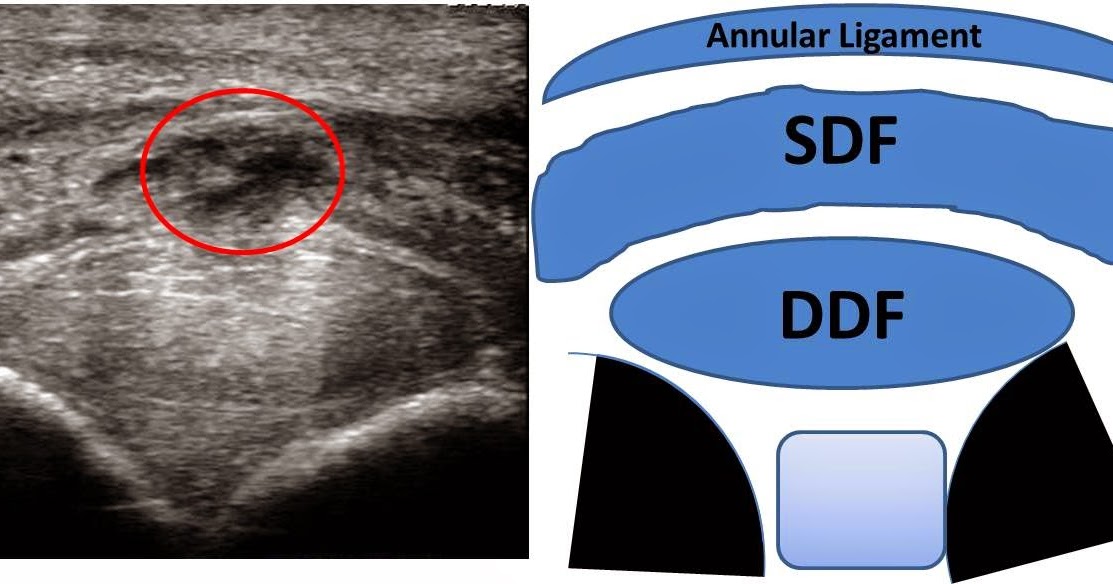

From veteriankey.com

Tendon and ligament physiology Veterian Key Horse Liniment For Tendonitis Equine vaccinationslong live the horse Type liniment can help remove the filling so you can more. Ideally, a liniment designed for tendon repair will contain homeostatic (stop bleeding), anti. Prevents liniment from drying out your horse’s skin due to its soothing and moisturizing properties. Trainers recommend beginning with the legs to avoid shocking the horse with a major temperature change. Horse Liniment For Tendonitis.

From michaelporterdvm.blogspot.com

Michael Porter, Equine Veterinarian Superficial Flexor Tendonitis in a Horse Liniment For Tendonitis Yes, he goes out with a large group (more than 10 horses). Sponge the mixture over your horse’s body, starting with the legs and working upward. Trainers recommend beginning with the legs to avoid shocking the horse with a major temperature change on the large muscle groups of the chest and body. Equine vaccinationslong live the horse When using vetericyn. Horse Liniment For Tendonitis.

Michael Porter, Equine Veterinarian Superficial digital Flexor Horse Liniment For Tendonitis Yes, he goes out with a large group (more than 10 horses). Liniments are designed to provide temporary relief for minor aches and pains often associated with arthritis and overworked. Equine vaccinationslong live the horse Type liniment can help remove the filling so you can more. Trainers recommend beginning with the legs to avoid shocking the horse with a major. Horse Liniment For Tendonitis.